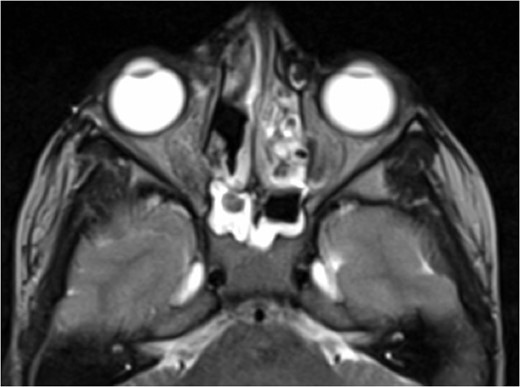

A 6-year-old boy with a background of asthma presented to a tertiary paediatric unit in May 2016 with a 3-day history of right eye pain, proptosis and erythema under the care of the ENT team. A provisional diagnosis of a periorbital cellulitis was made secondary to ethmoid sinusitis and management with intravenous antibiotics (ceftriaxone), intranasal steroids, saline douches and topical oxyxlometazoline was initiated. Ophthalmological assessment demonstrated normal colour vision, acuity and light reflexes bilaterally but also proptosis-related ophthalmoplegia. Computed tomography (CT) imaging of the orbits and paranasal sinuses demonstrated complete opacification of the right-sided paranasal sinuses and compromise of the right frontal and ostiomeatal unit. In addition there was an expansile abnormality centred on the ethmoidal labyrinth with bony remodelling of the lamina papyracea and a subperiosteal collection adjacent to the medial orbital wall (Figs 1 and 2). The most likely diagnosis was felt to be an infective process with mucopyocele formation complicated by a subperisoteal post-septal collection. An MRI scan with gadolinium of the orbits and sinuses confirmed the unilateral pattern of sinus opacification within the right frontal, ethmoids and maxillary sinus. The lesion demonstrated multiple fluid–fluid levels and peripheral enhancement (Figs 3 and 4). The patient was treated by endoscopic drainage of the lesion, which revealed only blood. He initially had some improvement of his proptosis but recurred within a few days and so further, more extensive endoscopic debridement was performed.

Axial T2 weighted sequence demonstrating the presence of multiple fluid filled levels (short white arrow) within the expansile lesion and smaller cyst present within the larger cyst (long white arrow).